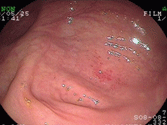

胃の中央付近から出口にかけて、出血性びらんが多発しています。

この方の背景胃粘膜には炎症も萎縮もなく、ピロリ菌陰性と考えられました。